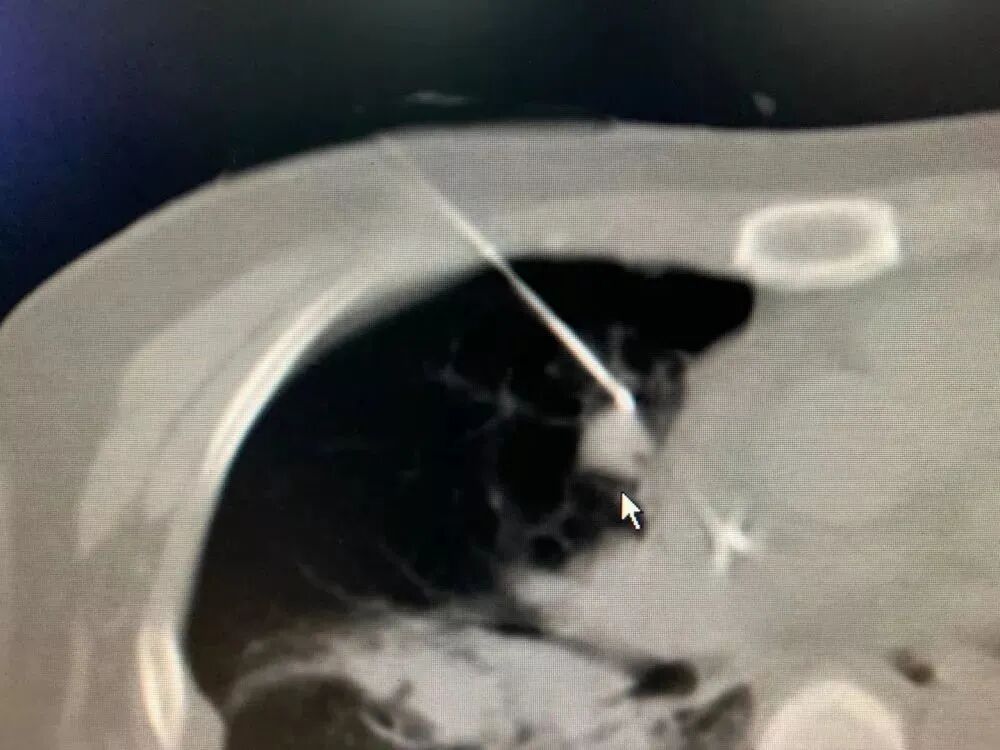

之前有一位肠癌患者,经历手术和放化疗后,发生了肺转移。肿瘤虽然不大,却长在了心脏旁边。如果直接开刀,风险极高;直接做冷冻消融,又可能误伤心脏。最终我们决定采用“钓鱼执法”冷冻消融术。

手术中,我用一根冷冻针“钓”住肿瘤,像收起鱼线那样,慢慢把它从心脏附近牵引到更安全的位置,再实施冷冻消融。整个过程必须极度谨慎,因为心脏周围血管丰富,稍有不慎就可能引发大出血。